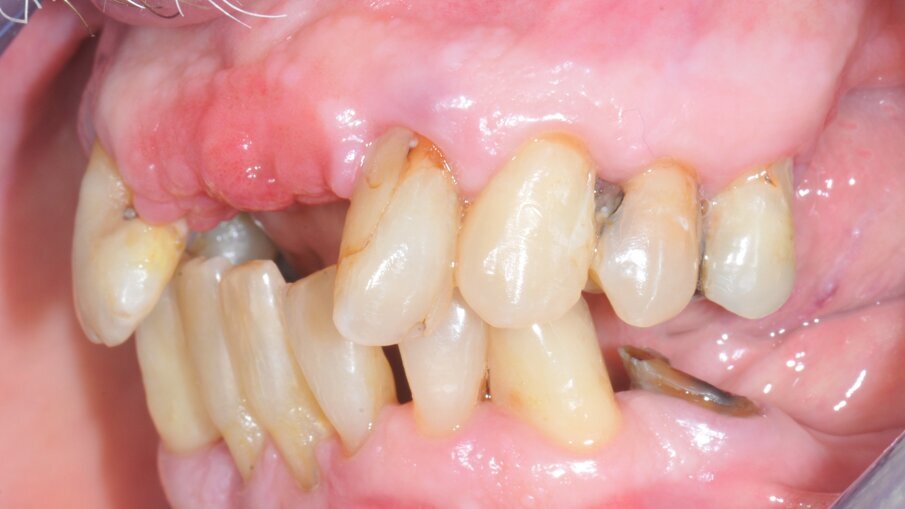

Dopo l’estrazione degli elementi residui, sono quindi stati inseriti i 4 impianti mono-componente con MUA integrato FIXO (OXY Implant Dental System, Colico, Italia) con un torque d’inserzione maggiore di 35 N/cm. Gli alveoli post-estrattivi sono stati riempiti con osso bovino deproteinizzato (Bio-oss Geislich Wholusen CH) così da ridurre il rimodellamento osseo12. La gestione dei tessuti molli è stata ottenuta mediante un innesto connettivale con tecnica bilaminare a livello dell’impianto in posizione 11. Sono stati avvitati gli abutment provvisori direttamente alla piattaforma protesica integrata per poter procedere poi a un corretto posizionamento della struttura protesica grazie a un incollaggio intraorale. La protesi è stata fissata ai monconi provvisori con una resina composita auto foto polimerizzabile (Relyx Unicem 2 3M Minnesota USA) direttamente in bocca, ottenendo così la passivazione della stessa (Figg. 4a, 4b).

Dopo 4 mesi, è stato necessaria una correzione estetica dei tessuti molli con un ulteriore innesto connettivale bilaminare per migliorare lo spessore dei tessuti molli in area 22 per ottenere un migliore profilo d’emergenza del restauro protesico in corrispondenza dell’area dell’incisivo laterale di sinistra. Dopo il periodo di guarigione per l’osteointegrazione, è stata acquisita una scansione intraorale delle due arcate per replicare i parametri estetici e funzionali determinati per la riabilitazione provvisoria, secondo la tecnica di digital cross-mounting, e per rilevare la posizione degli impianti, utilizzando 4 scan body. I parametri estetici e funzionali sono stati riprodotti dalla protesi provvisoria immediata.